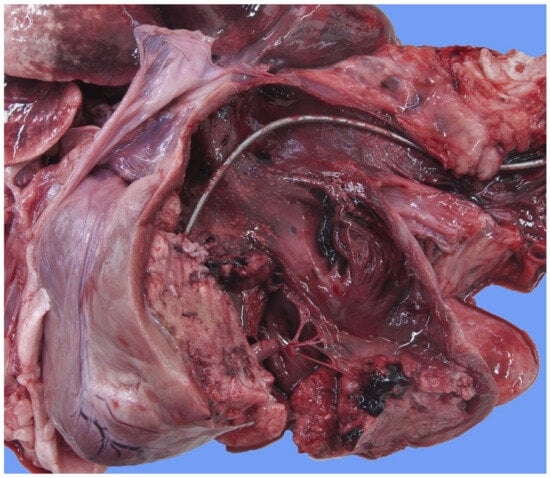

Focally extending throughout the right ventricular lumen and partially incorporating the chordae tendineae and tricuspid valve leaflets, was a large (6 × 4 × 4 cm) thrombus adhered to the endocardium. A length of approximately 3 cm of the pacing electrode was embedded within the thrombus (Figure 7). The myocardium of the adjacent interventricular septum and free ventricular wall showed patchy white discoloration. The site of the tip of the electrode was visible in the apex as a small, slightly indented, firm, white area of connective tissue. Thrombus material filled the lumens of the right and left pulmonary arteries (Figure 8). The lungs were mildly congested and edematous. There was moderate congestion in the liver and mild ascites.

Figure 7.

Necropsy shows the right side of the heart and mediastinum of the dog. The walls of the jugular vein, the right atrium and the right ventricle are open allowing the visualization of the lumen. The pacemaker lead disappears in the pale soft tissue mass that fills the right ventricular chamber.